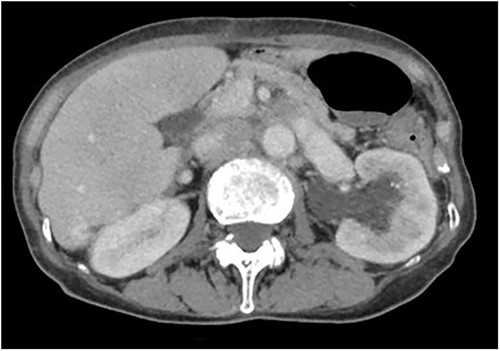

A 78-year-old woman (height, 161 cm; weight, 35 kg) had undergone total gastrectomy for gastric cancer; pathological examinations had revealed signet ring cell carcinoma with invasion into the serosa. One year and 4 months after the surgery, she presented to our hospital with fever, anorexia and weight gain. Computed tomography (CT) revealed left ureteral stricture and hydronephrosis caused by recurrent peritoneal dissemination (Fig. 1). Blood tests revealed decreased renal function and an increase in the inflammatory response. Based on these findings, a diagnosis of left obstructive acute pyelonephritis was made, prompting a decision to place a ureteral stent to relieve the obstruction. Using a flexible cystoscope fluoroscopically, a 6 Fr, 24 cm double-J ureteral stent was inserted into the left ureter. The guidewire passed smoothly, and good coiling was achieved both proximally and distally with no apparent complications (Fig. 2). Two weeks after stent placement, the patient recovered with improvements in left hydronephrosis and renal function.

A post-operative plain abdominal X-ray; the ureteral stent is properly placed as seen in a plain abdominal X-ray.